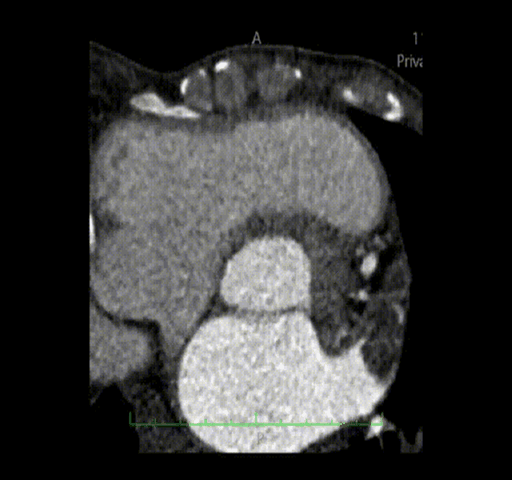

主动脉根部解剖动态图: